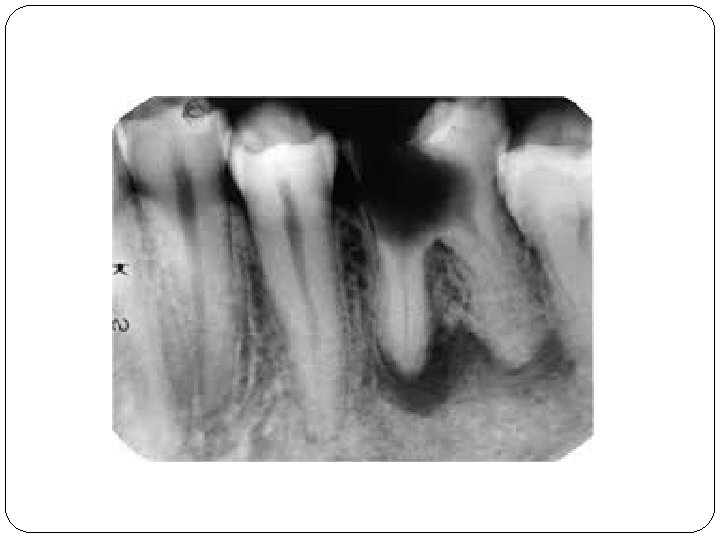

II/C Abcessus periapicale chronica �abgekapselte Ansammlung von Eiter �Symptome: spontaner Zahnschmerz, Perkussionsschmerz Fistula, Gaumenschwellung Eiterbeule an der Gaumen �Röntgen: Irregulare und unscharfe Grenze, Aufhellung, (Granuloma und Zyst sind dunkler)